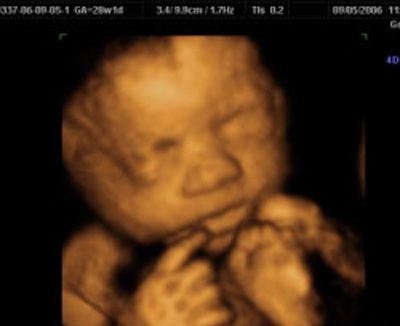

УЗИ: 28 неделя беременности

Начался третий и заключительный триместр беременности. Вес плода уже превышает один килограмм. На ультразвуковом исследовании специалисты оценивают его размеры и положение в матке. С этой недели малыш начинает занимать ту позицию, из которой, скорее всего, будет рожден. Тем не менее, если на УЗИ врач сообщил, что ребенок находится в неправильном положении, не стоит паниковать — в матке все еще достаточно пространства, чтобы он мог изменить свою ориентацию.

Фотографии, полученные во время УЗИ на 42 неделе, могут показать, как выглядит плод в этот период. Обычно на изображениях можно увидеть хорошо сформированные черты лица, конечности и другие анатомические детали. Эти изображения могут стать ценным воспоминанием для родителей, ожидающих встречи с малышом.